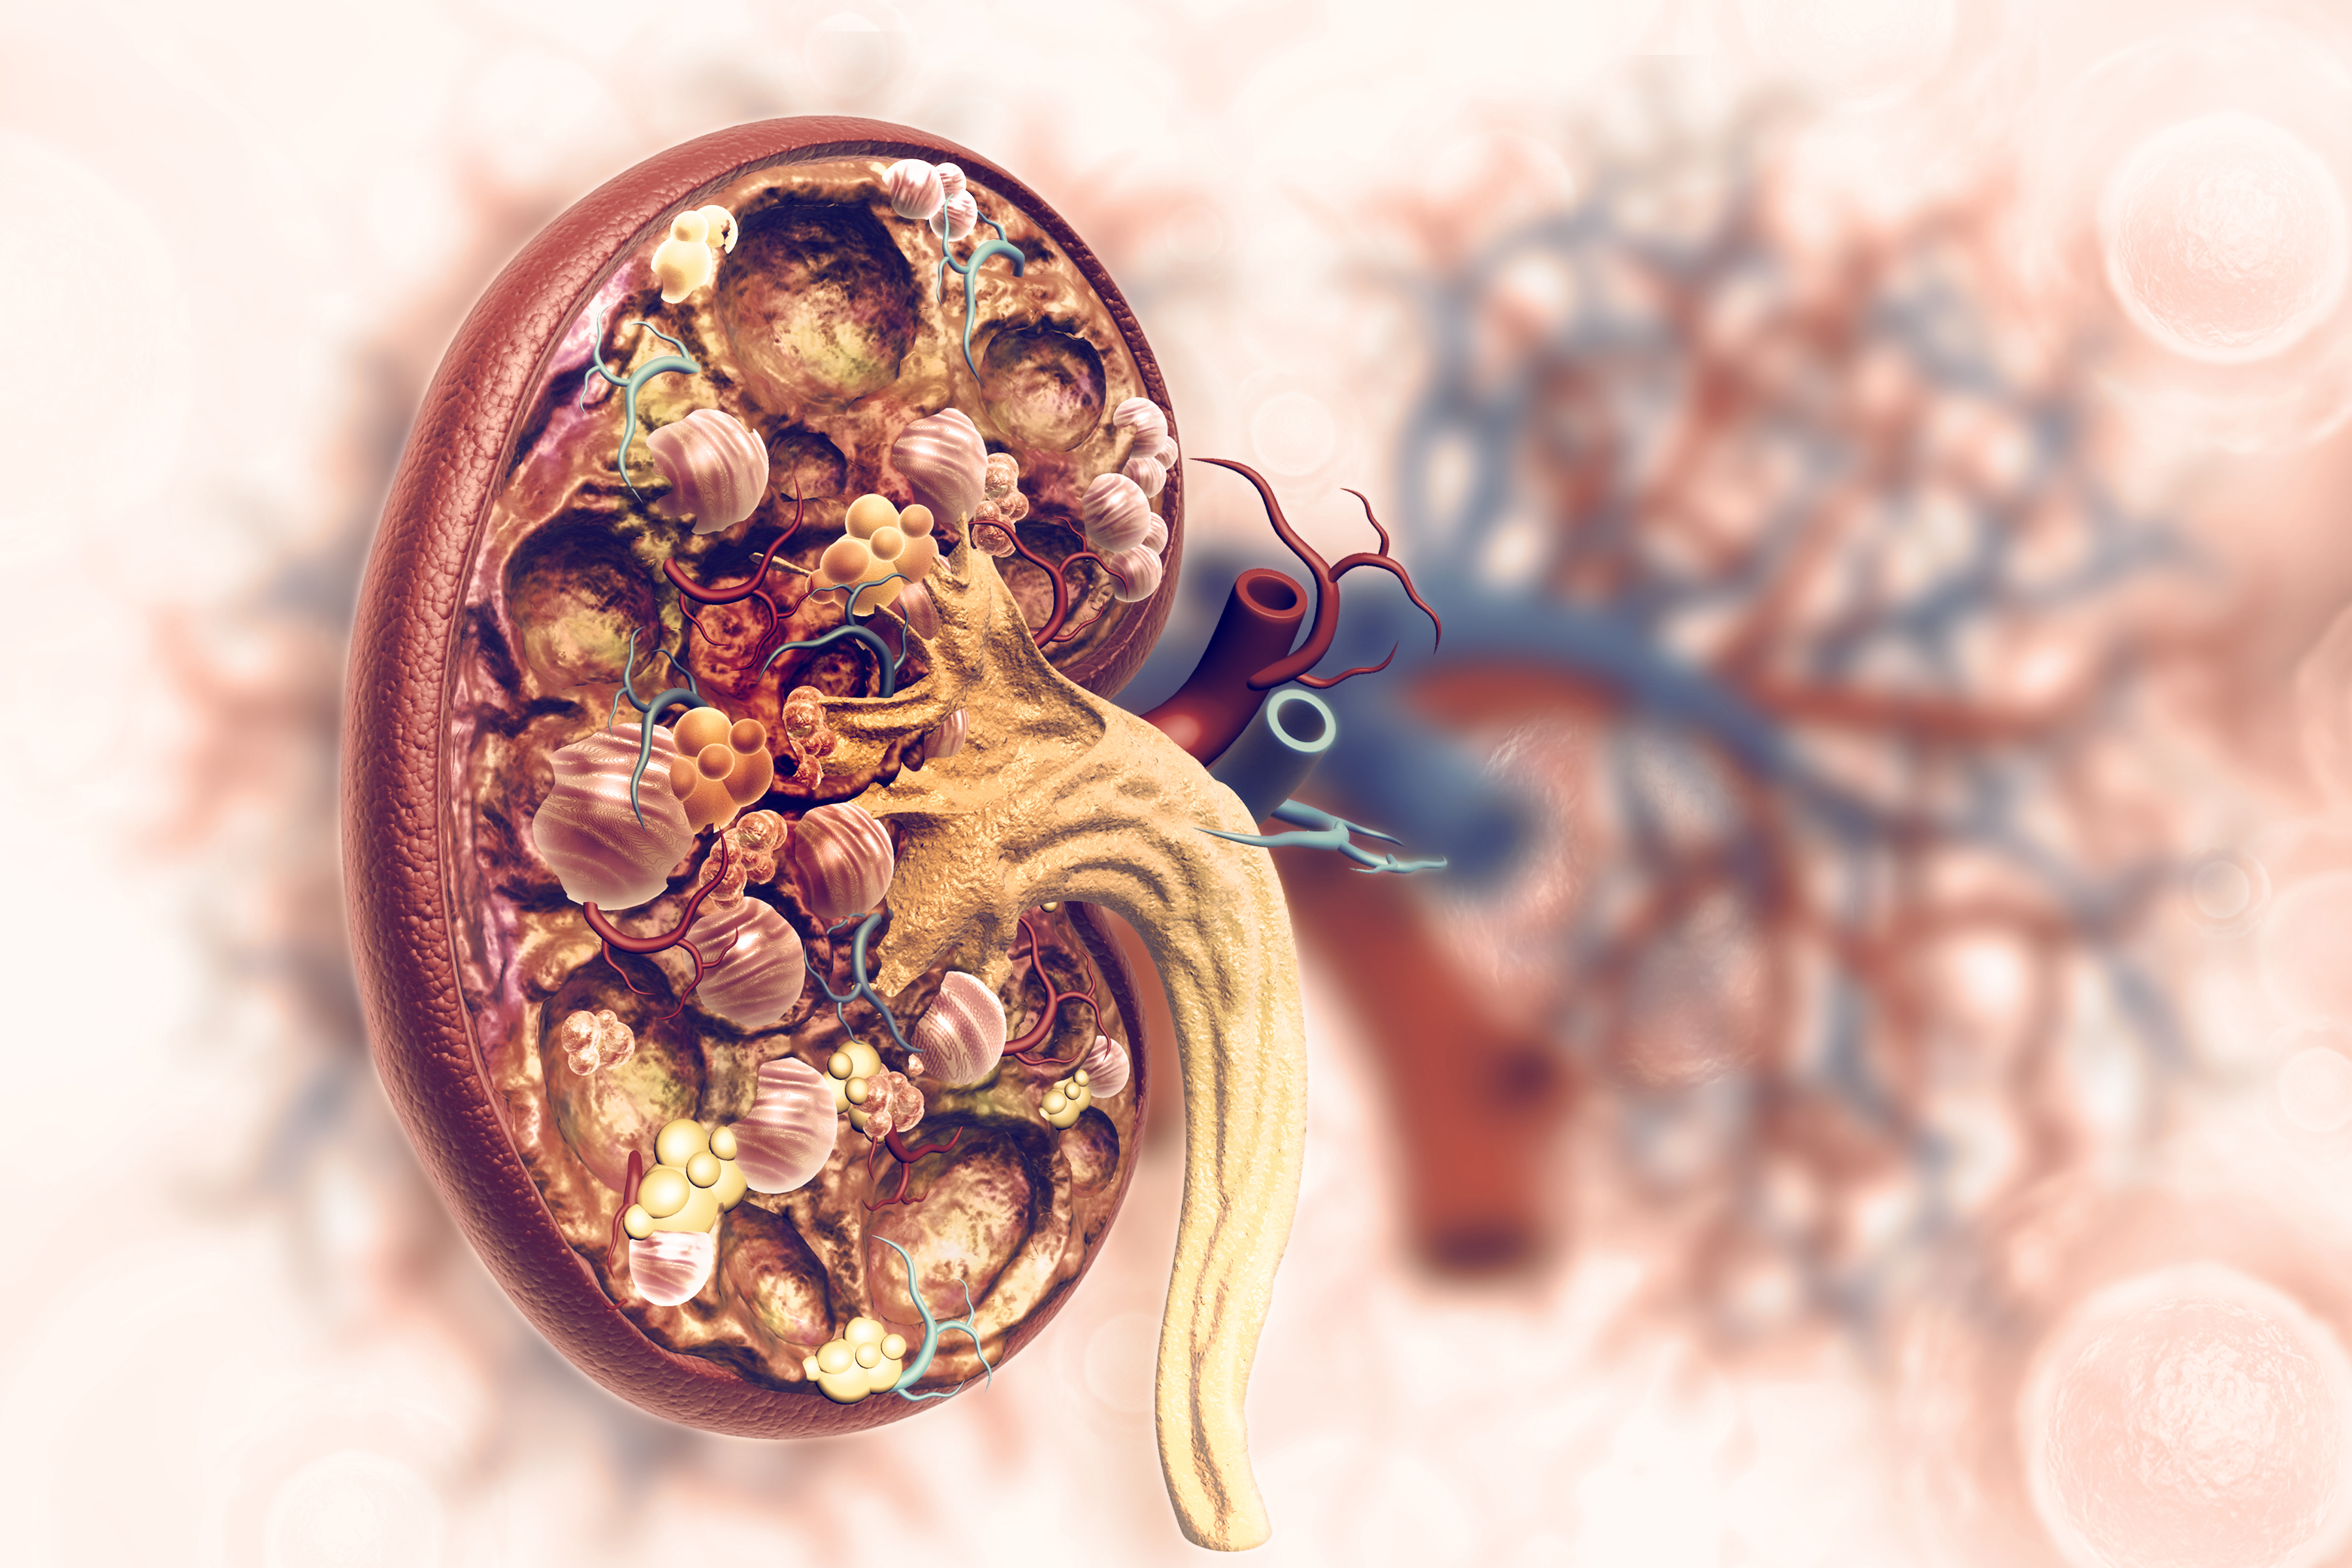

Les reins, à l'instar d'autres organes, ont la capacité inhérente de récupérer d'une agression aiguë (insuffisance rénale aiguë). En effet après agression (toxique par exemple), les cellules dites « épithéliales tubulaires », qui constituent la structure fonctionnelle des reins, meurent. Les cellules survivantes vont se mettre à proliférer de manière très intense pour repeupler en environ trois semaines les reins (réponse rénale dite adaptée). Cependant, si l’agression rénale est sévère ou prolongée, les cellules tubulaires n’arrivent pas à suffisamment proliférer pour compenser les pertes initiales. Ces cellules vont se mettre synthétiser des facteurs qui favorisent l’apparition de cicatrices fibreuses (fibrose) dans les reins (réponse rénale dite inadaptée). Cette fibrose sera responsable d’une altération de la fonction rénale, c’est-à-dire d’une insuffisance rénale chronique. Une fois ces mécanismes mis en place, la maladie rénale chronique, irréversible, s’auto entretient et progresse d’elle-même. Les mécanismes cellulaires impliqués dans l’apparition de la fibrose rénale sont très mal connus.